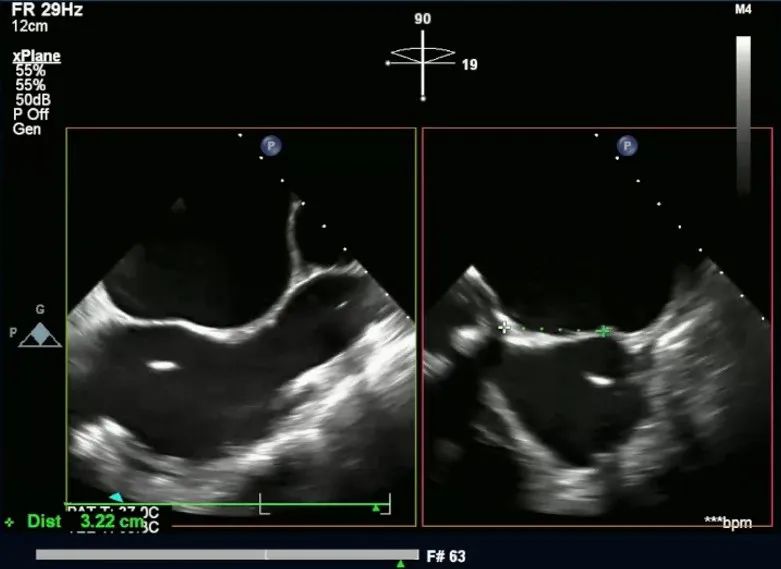

预穿刺点距离主动脉3.22cm

预穿刺点距离下腔1.61cm